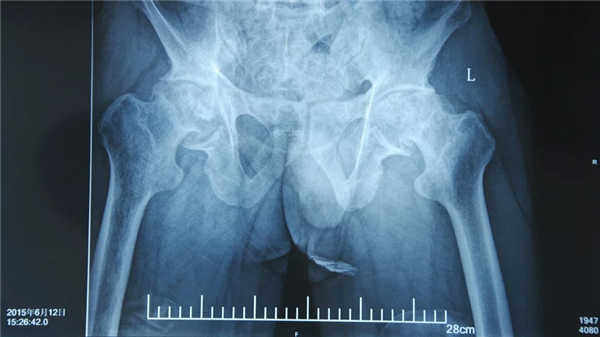

入院时:双侧股骨头破坏严重,存在塌陷、骨缺损、骨密度高等问题